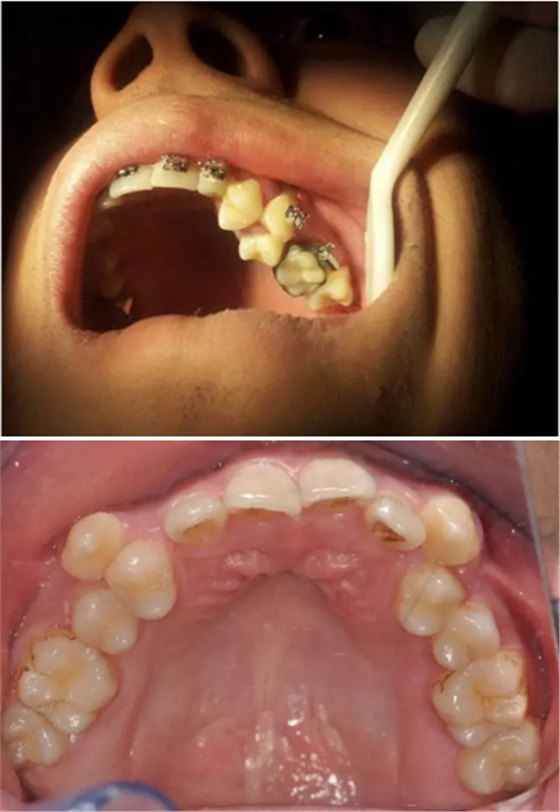

再看看逆襲的尖牙阻生。。。

小泥鰍

橫位

錯(cuò)位

大尺度異位